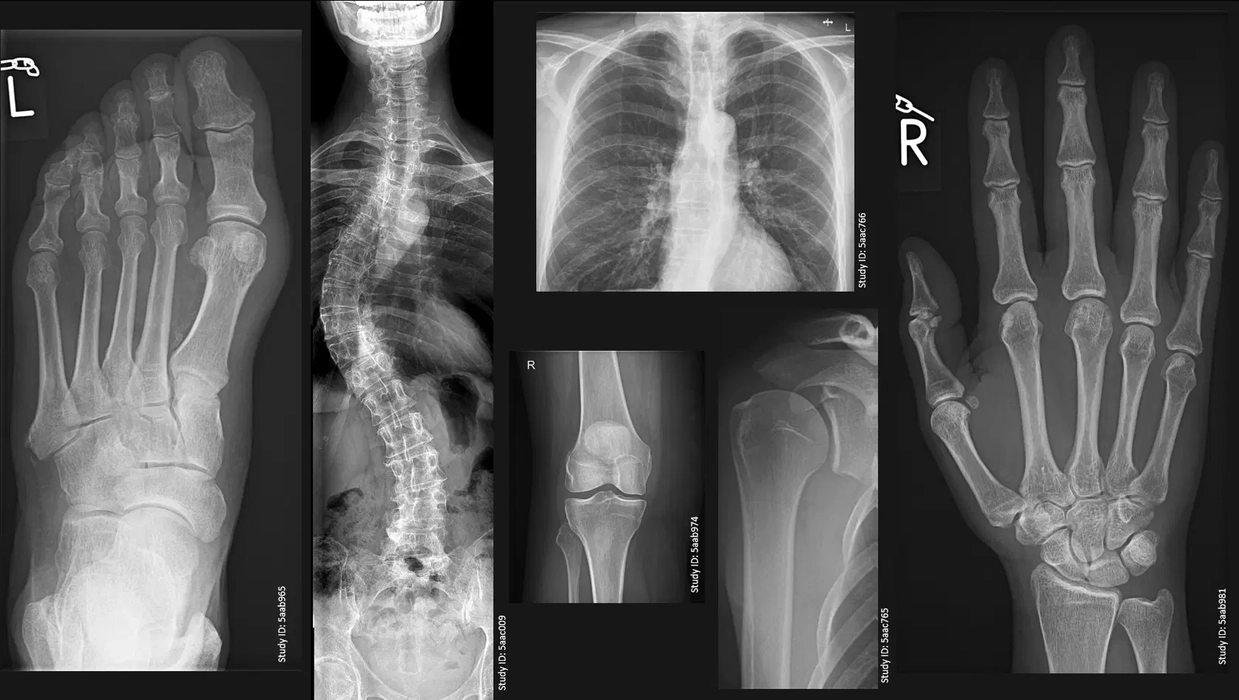

Ce preț are o radiografie de picior și când este necesară? Iată tot ce trebuie să știi!